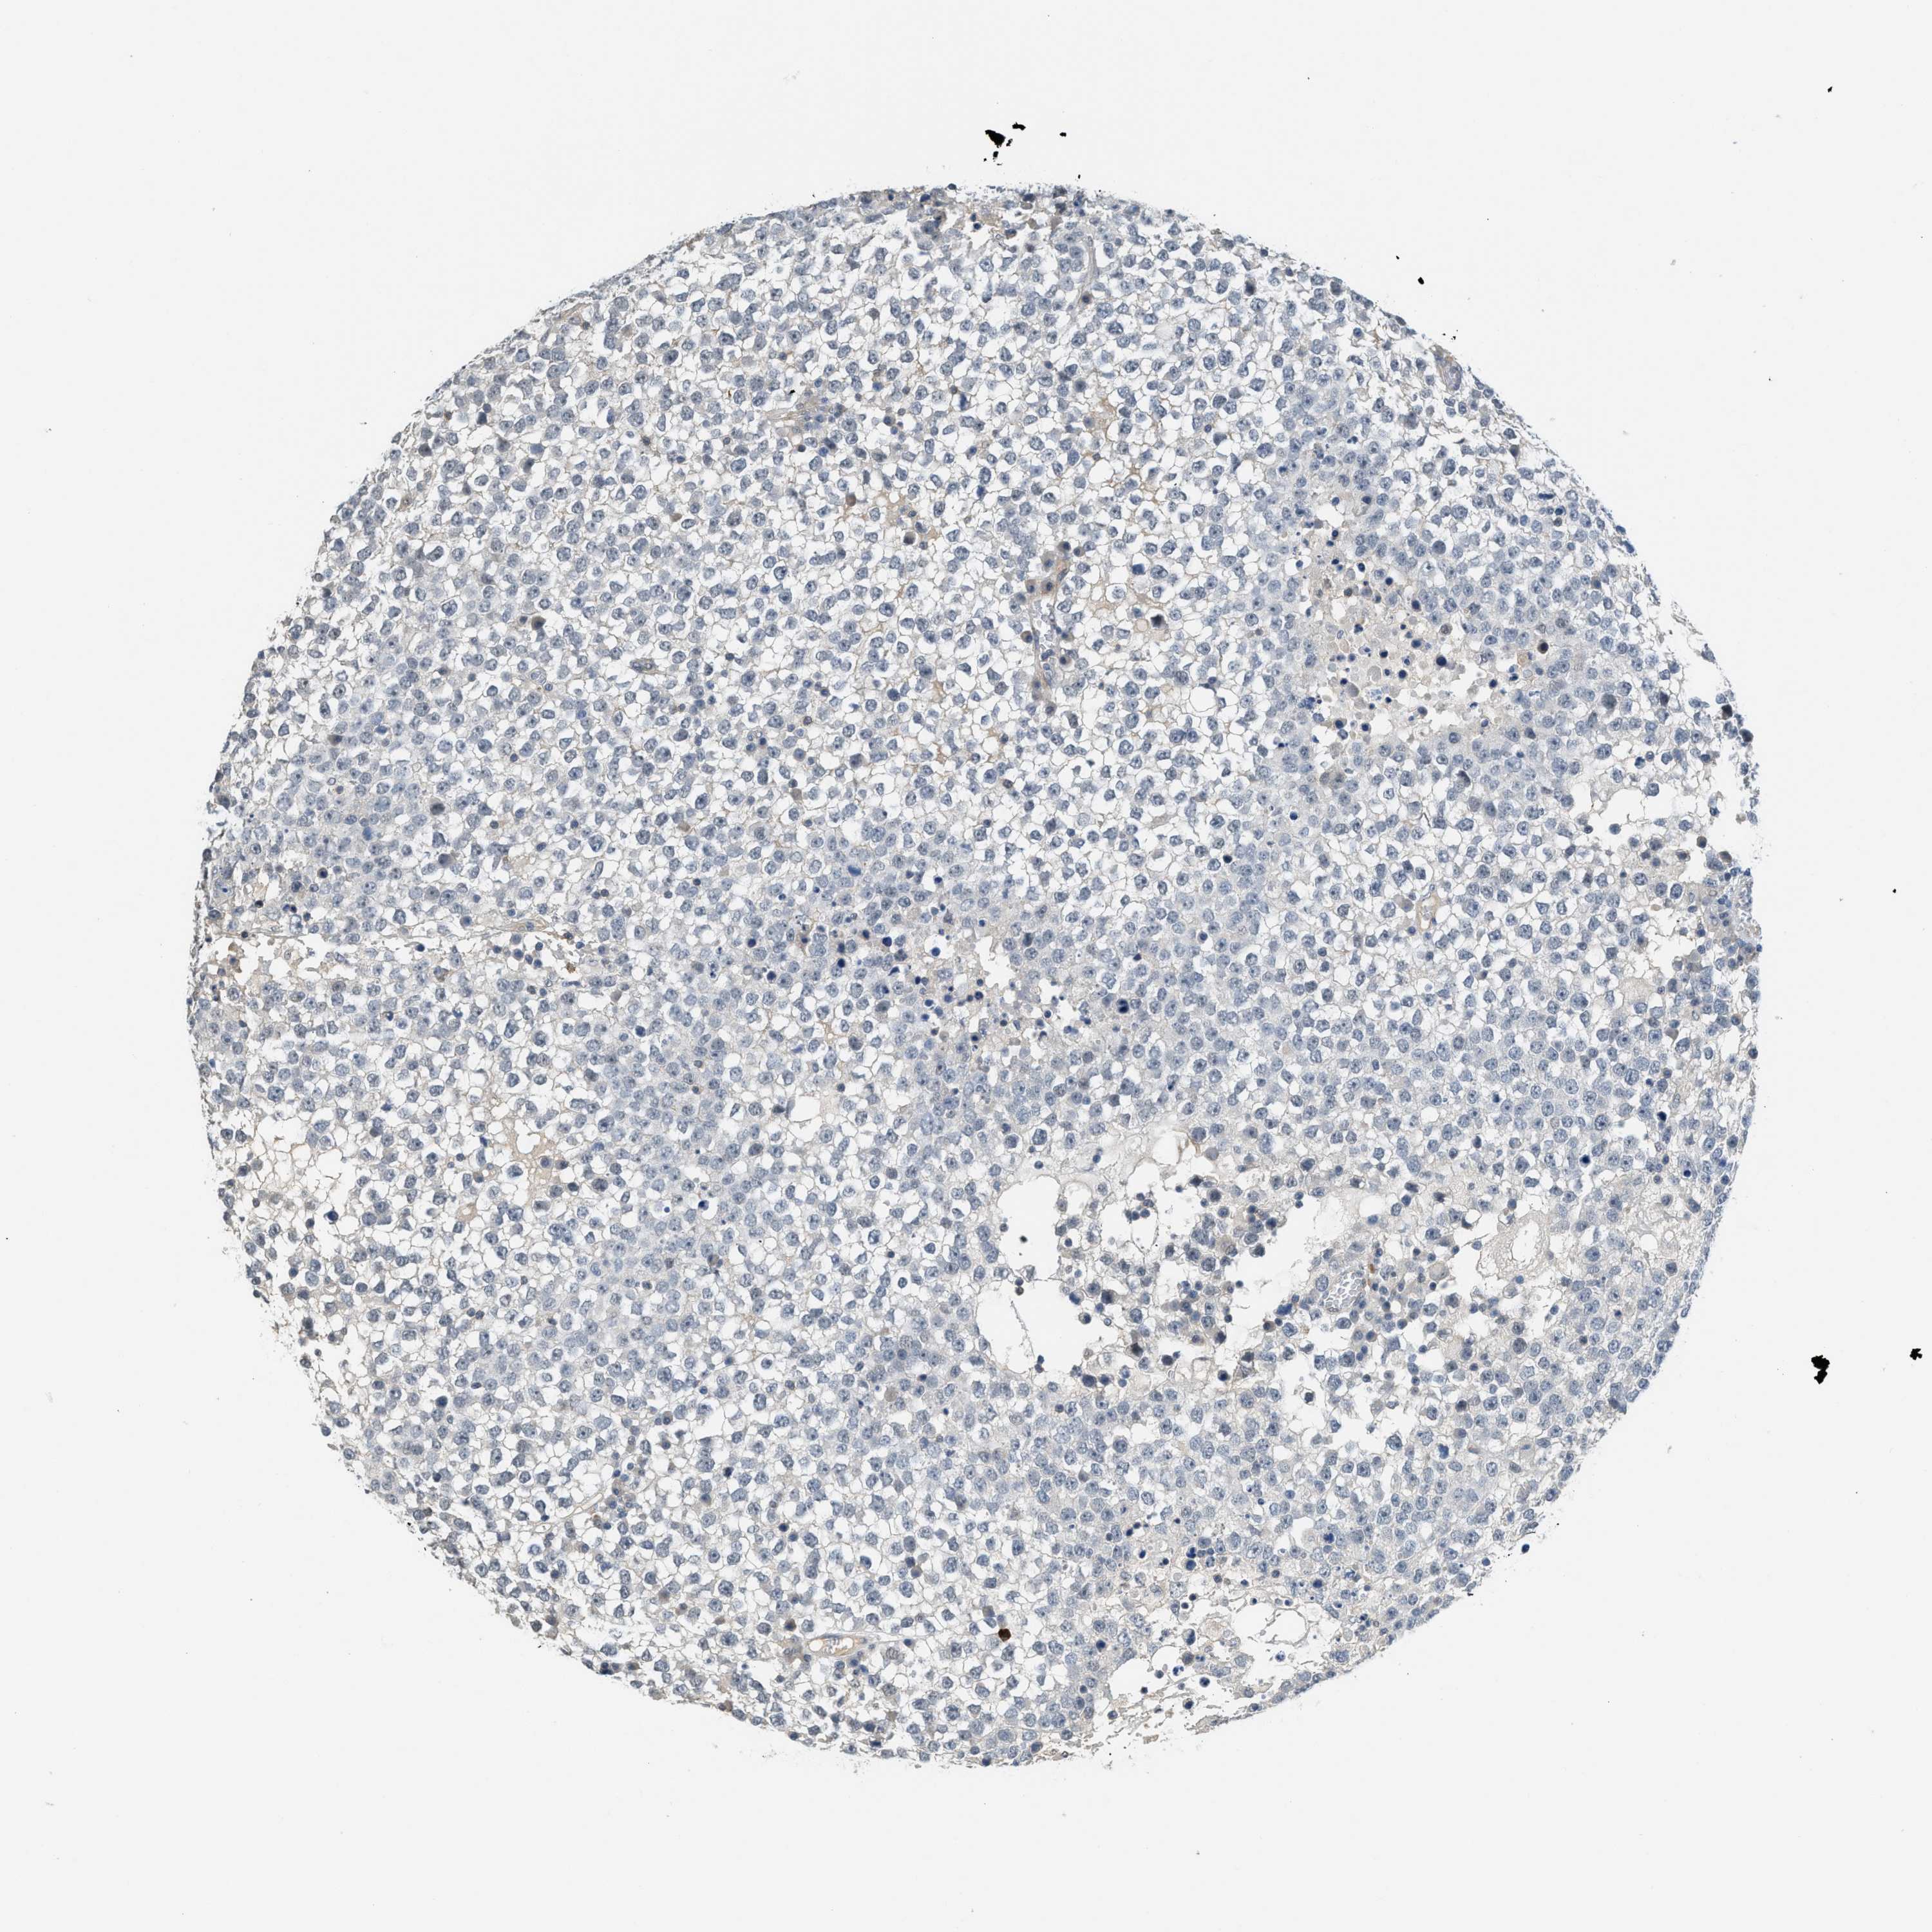

TESTIS CANCER - Protein expressioni

A mouse-over function shows sample information and annotation data. Click on an image to view it in a full screen mode. Samples can be filtered based on level of antibody staining by selecting one or several of the following categories: high, medium, low and not detected. The assay and annotation is described here.

Note that samples used for immunohistochemistry by the Human Protein Atlas do not correspond to samples in the TCGA dataset.

Antibody stainingi

Antibody staining in the annotated cell types in the current human tissue is reported as not detected, low, medium, or high, based on conventional immunohistochemistry profiling in selected tissues. This score is based on the combination of the staining intensity and fraction of stained cells.

Each image is clickable and will lead to virtual microscopy that enables deeper exploration of all samples and also displays staining intensity scores, fraction scores and subcellular localization as well as patient and tissue information for each sample.

Antibody HPA019184

Staining

High

Medium

Low

Not detected

Intensity

Strong

Moderate

Weak

Negative

Quantity

>75%

75%-25%

<25%

None

Location

Nuclear

Cytoplasmic/membranous

Cytoplasmic/membranous,nuclear

Carcinoma, Embryonal, NOS

Seminoma, NOS